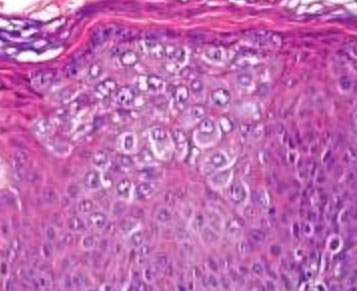

Pagetoid spread in SCC

Pagetoid spread: melanocytes growing upward toward skin surface

- seen in Paget disease of the nipple, Paget disease of the skin, melanoma, and SCC